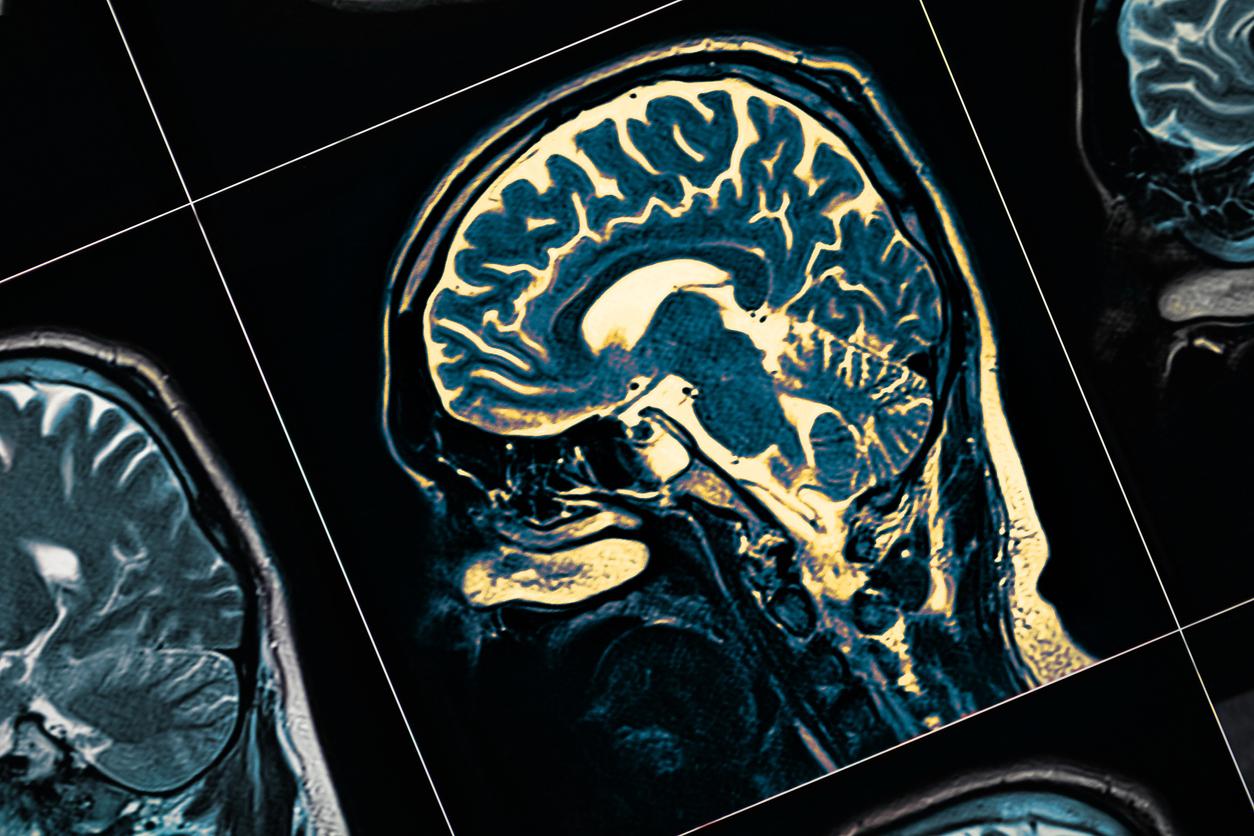

- Les personnes qui développent une schizophrénie ont une fragilité biologique (cerveau et corps), mais elles sont aussi soumises à des stress environnementaux.

Cette modification de conscience est provoquée par la déficience d’un ou deux sens.